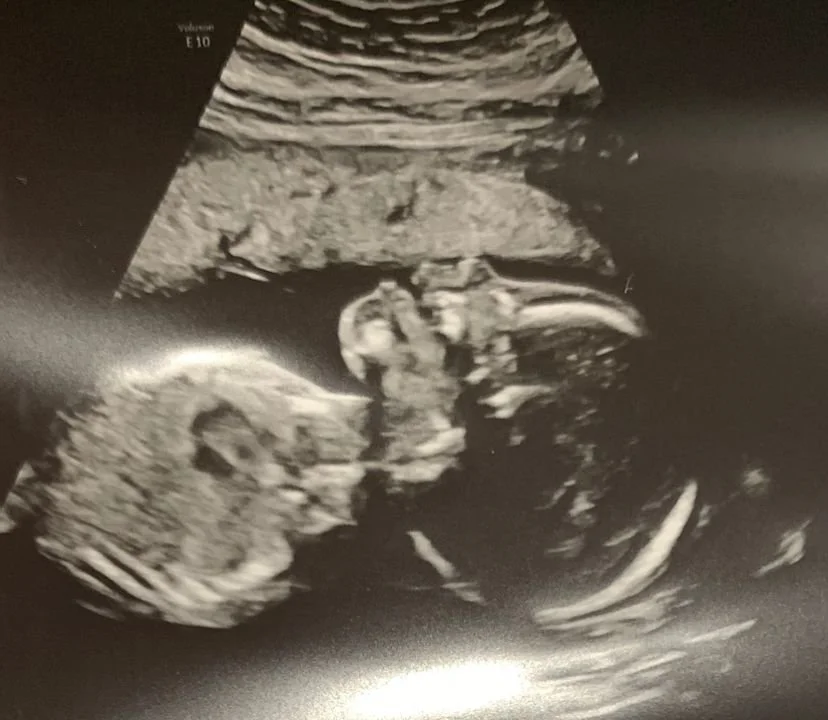

We are also excited to welcome another new member to our family next year—a baby boy! Due end of March 2022, we are so excited to welcome this new addition and kindly ask for your prayers that God protects both the baby and Jennifer throughout the pregnancy and beyond.